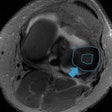

CAD boosts breast MRI sensitivity